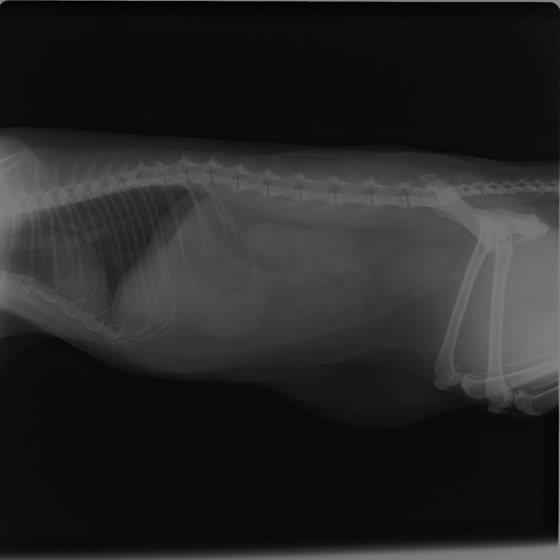

4歳 アメリカンショートヘアー

主訴:3日前から嘔吐が続き、食欲も落ちてきたのこと。

対症療法(症状に対する治療)に反応しないため、精査を実施。

一般血液検査:問題なし

単純レントゲン検査:胃内ガス陰影・腸内ガスが少量認められる。

嘔吐が改善しないため、消化管バリウム造影検査を実施。

消化管バリウム造影レントゲン

バリウム造影3時間経過するも、胃内からバリウム排泄なく同日内視鏡検査を実施。

内視鏡検査結果:内視鏡下にて、バスケット鉗子を用いて摘出。

症例は、机の上に置いていたピスタチオのお菓子を誤飲していました。その後の経過は良好です。本症例は、内視鏡下にて摘出ができましたが、球状・立体などの大きな異物は、腸の途中で詰まりやすく、内視鏡下での摘出が困難な場合もあります。その際は、開腹下にて腸内の異物を摘出しなくてはなりません。動物たちは、思わぬ物を誤飲することがあります。お留守番時・就寝時は、誤飲をしやすい時間帯ですので注意しましょう。